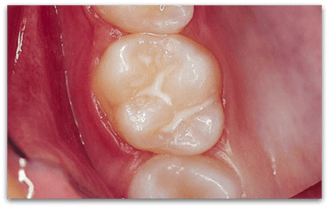

Versiegelte Fissur

Versiegelte Fissur (© Doc S)

Versiegelung an einem Backenzahn: Der Versiegelungs-Kunststoff dichtet die Fissuren ab, so dass sich kein Zahnbelag und keine Bakterien festsetzen können.